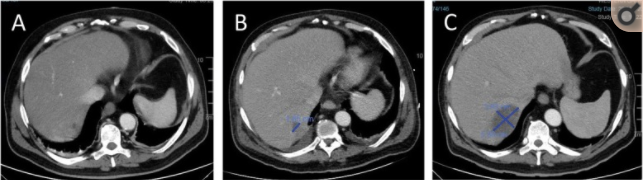

患者出院两周后因再次出现腹痛症状,行超声内镜检查,发现胆囊结石,胆汁淤积,同时发现胆总管轻度扩张,两处充盈缺损,遂行ERCP治疗,术中切开十二指肠乳头,网篮取出胆总管结石,术后24小时患者出现寒战发热症状,肝功能异常明显(AST224U/L,ALT121U/L,ALP160U/L,GGT570U/L),经验性使用头孢和甲硝唑治疗,但寒战发热症状并未好转,血象持续升高,术后第三天行全腹CT检查,发现肝脏VII段可见一低密度病灶,如图1。

图1 ERCP术后腹部CT可见肝脏VII段可见一低密度病灶,3天(a),7天(b),26天(c)

术后第8天,血培养结果回报克雷伯杆菌及肠球菌感染,将抗生素升级为亚胺培南,但患者仍有腹痛症状,无腹膜炎体征,C-反应蛋白160mg/L,白细胞计数13x109,中性粒细胞比例83%,再次复查全腹CT,发现肝脏VII段低密度灶增大,考虑化脓性肝脓肿,如图1b,但此次增强CT发现患者右侧腰大肌脓肿,如图2a,决定继续抗炎及对症治疗,未行引流,两天后,患者腹痛减轻,肝功能基本恢复正常。患者出现腰痛及行走困难,查体发现L4-L5棘突压痛,行腰椎磁共振(MRI),出现了脊髓神经根压迫,并在ERCP术后第19天出现了骨脓肿,转至骨科行手术治疗,术中行L5椎间盘局部切除,骨膜外脓肿切开引流,留置引流管。术后脓液培养为克雷伯杆菌阳性,继续抗炎治疗,但患者仍有发热症状,术后第7天出现肝脓肿,病灶为肝VII段低密度不规则病变,大小约4.8cm,如图1C。后续患者继续抗炎治疗6周,引流通畅,切口预后良好,复查腹部CT,脊髓MRI,肝脓肿和骨脓肿消失,出院6周后再次行腹腔镜胆囊切除术。